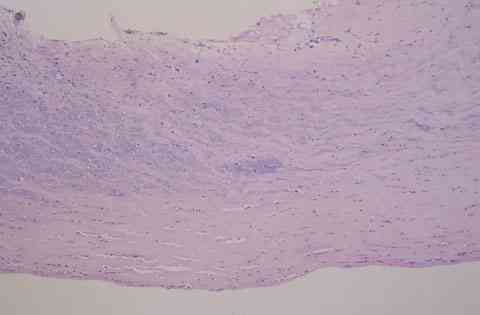

Figura 4

QUERATITIS BACTERIANA. CÓRNEA EDEMATOSA, CON CÉLULAS INFLAMATORIAS DE TIPO AGUDO Y MICROORGANISMOS INFILTRANDO TODO EL ESTROMA (PAS, 250x).